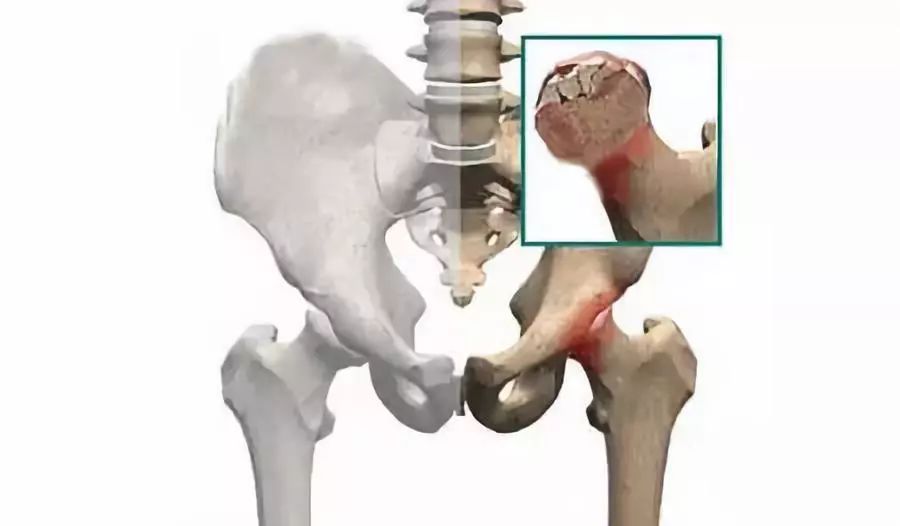

股骨头塌陷

是患者坏死的股骨头,已经塌陷变形

晚期股骨头塌陷,碎裂,变形,有的可造成髋关节半脱位,此时的疼痛与髋